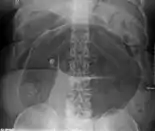

After taking a thorough history, the diagnosis of colonic volvulus is usually easily included in the differential diagnosis. Abdominal plain x-rays are commonly confirmatory for a volvulus, especially if a "bent inner tube" sign or a "coffee bean" sign are seen. These refer to the shape of the air-filled closed loop of colon which forms the volvulus. Should the diagnosis be in doubt, a barium enema may be used to demonstrate a "bird's beak" at the point where the segment of proximal bowel and distal bowel rotate to form the volvulus.

Coffee bean sign in a person with sigmoid volvulus